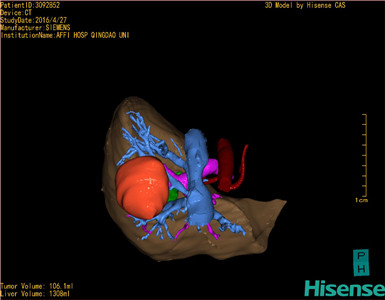

CT结果输入海信CAS系统后行3D重建及手术规划后,于2016-5-14全麻下行“肝VII+VIII段切除术”手术治疗:

术前三维重建及手术方案设计:

将0.625mm双源薄层CT资料的静脉期和动脉期Dicom格式文件导入海信CAS系统。

通过调节窗宽窗位调整CT序号,对肿瘤,肝实质,胆囊,下腔静脉,肿瘤,肝动脉、门静脉及肝静脉等进行三维重建;系统自动计算肿瘤体积和肝脏体积。

模拟手术操作,自动计算切除肿瘤体积。肝脏体积为1308ml,肿瘤体积为106.1ml,肿瘤体积为肝脏体积的8.1%,通过比对40-50岁正常肝脏体积为1368.38±279.24 ml,通过术前模拟手术,精准判断切除后剩余肝脏体积能耐受,避免肝衰竭发生。

术前手术方案的规划。

术前三维重建:

重建图片